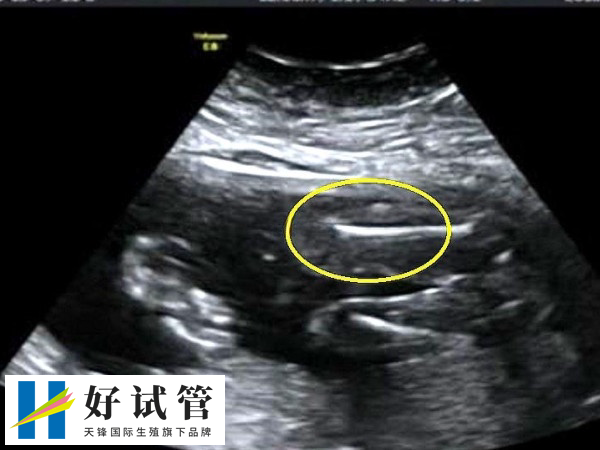

- 1. 第一次B超检查:通常在移植后约4周进行,这次检查主要用于确认妊娠,并查看胚胎的发育情况,如妊娠囊的大小、胚芽和胎心搏动的存在;

- 2. 第二次B超检查:这是在第一次B超检查后约1周进行,这次检查进一步确认胚胎的发育状态,并根据孕囊大小调整保胎药物的剂量;

- 3. 第三次B超检查:通常在怀孕11至13周进行,这次检查主要用于了解胎儿的整体发育情况,包括胎盘、羊水等,并进行必要的检查如nt(胎儿颈部透明度)检查。

总结来说,试管婴儿治疗过程中,通常需要进行三次B超检查,分别在移植后4周、5周和11至13周,以确保胚胎的正常发育,并在确认胎儿健康后转到产科进行常规的产前检查。